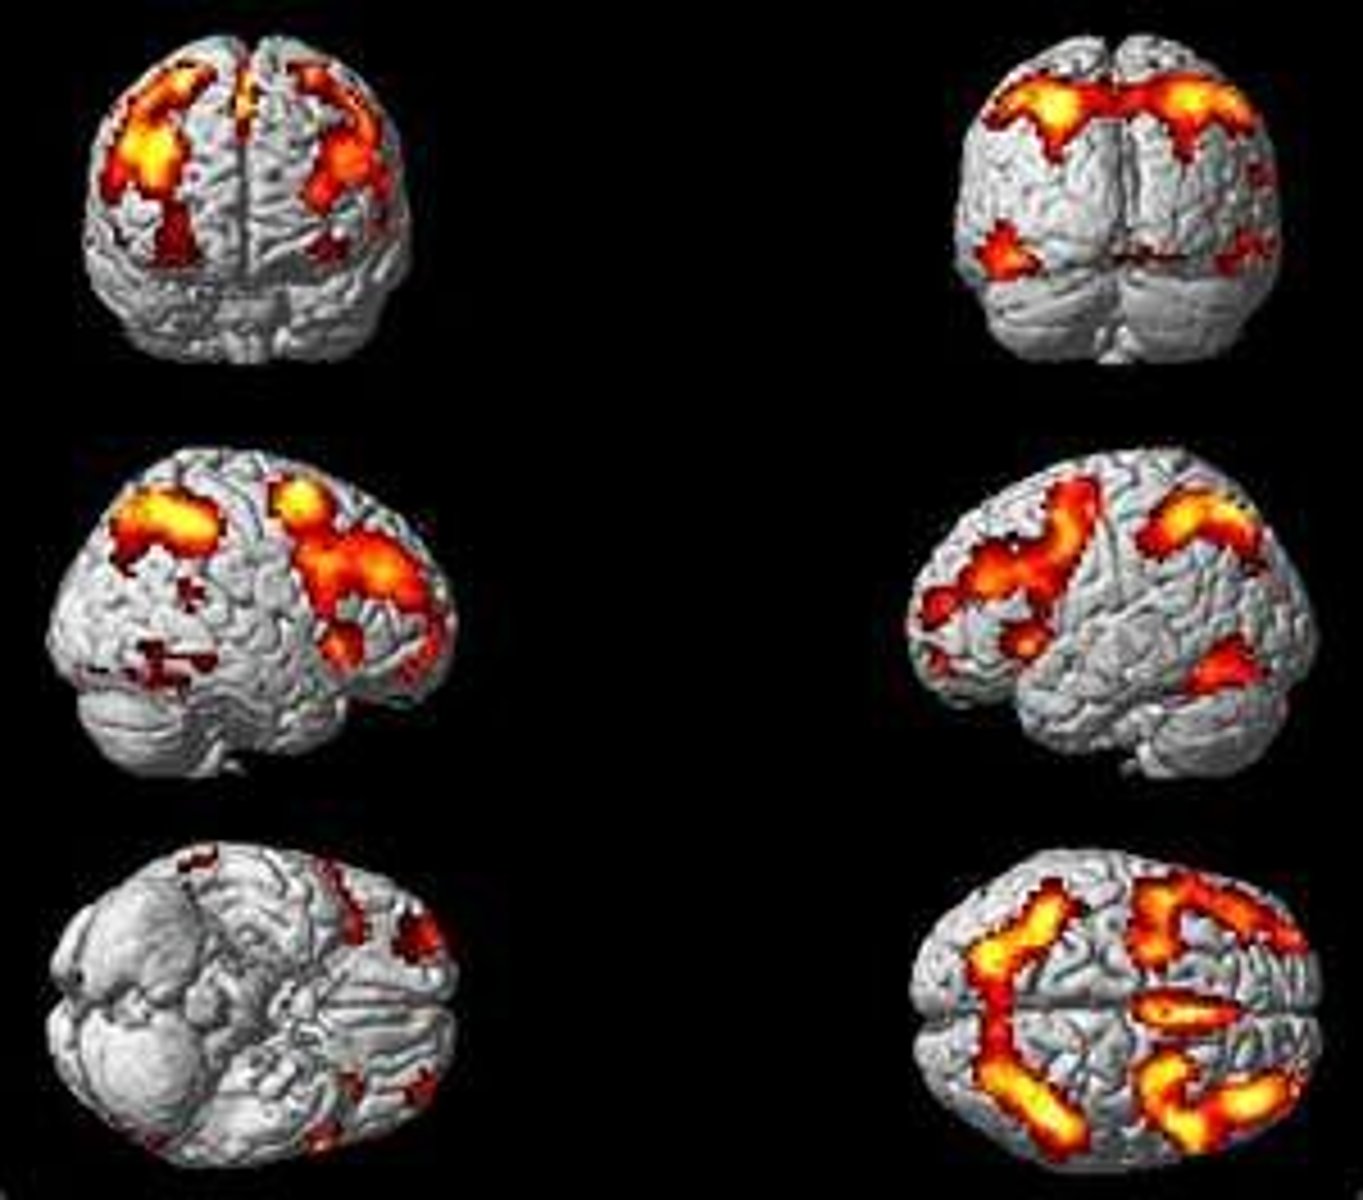

positron emission tomography (PET)

imaging technique that measures consumption of glucose-like molecules, yielding a picture of neural activity in different regions of the brain

PET (positron emission tomography)

A visual display of brain activity that detects where a radioactive form of glucose goes while the brain performs a given task.

fMRI (functional MRI)

A technique for revealing blood flow and, therefore, brain activity by comparing successive MRI scans show brain anatomy; fMRI scans show brain function.